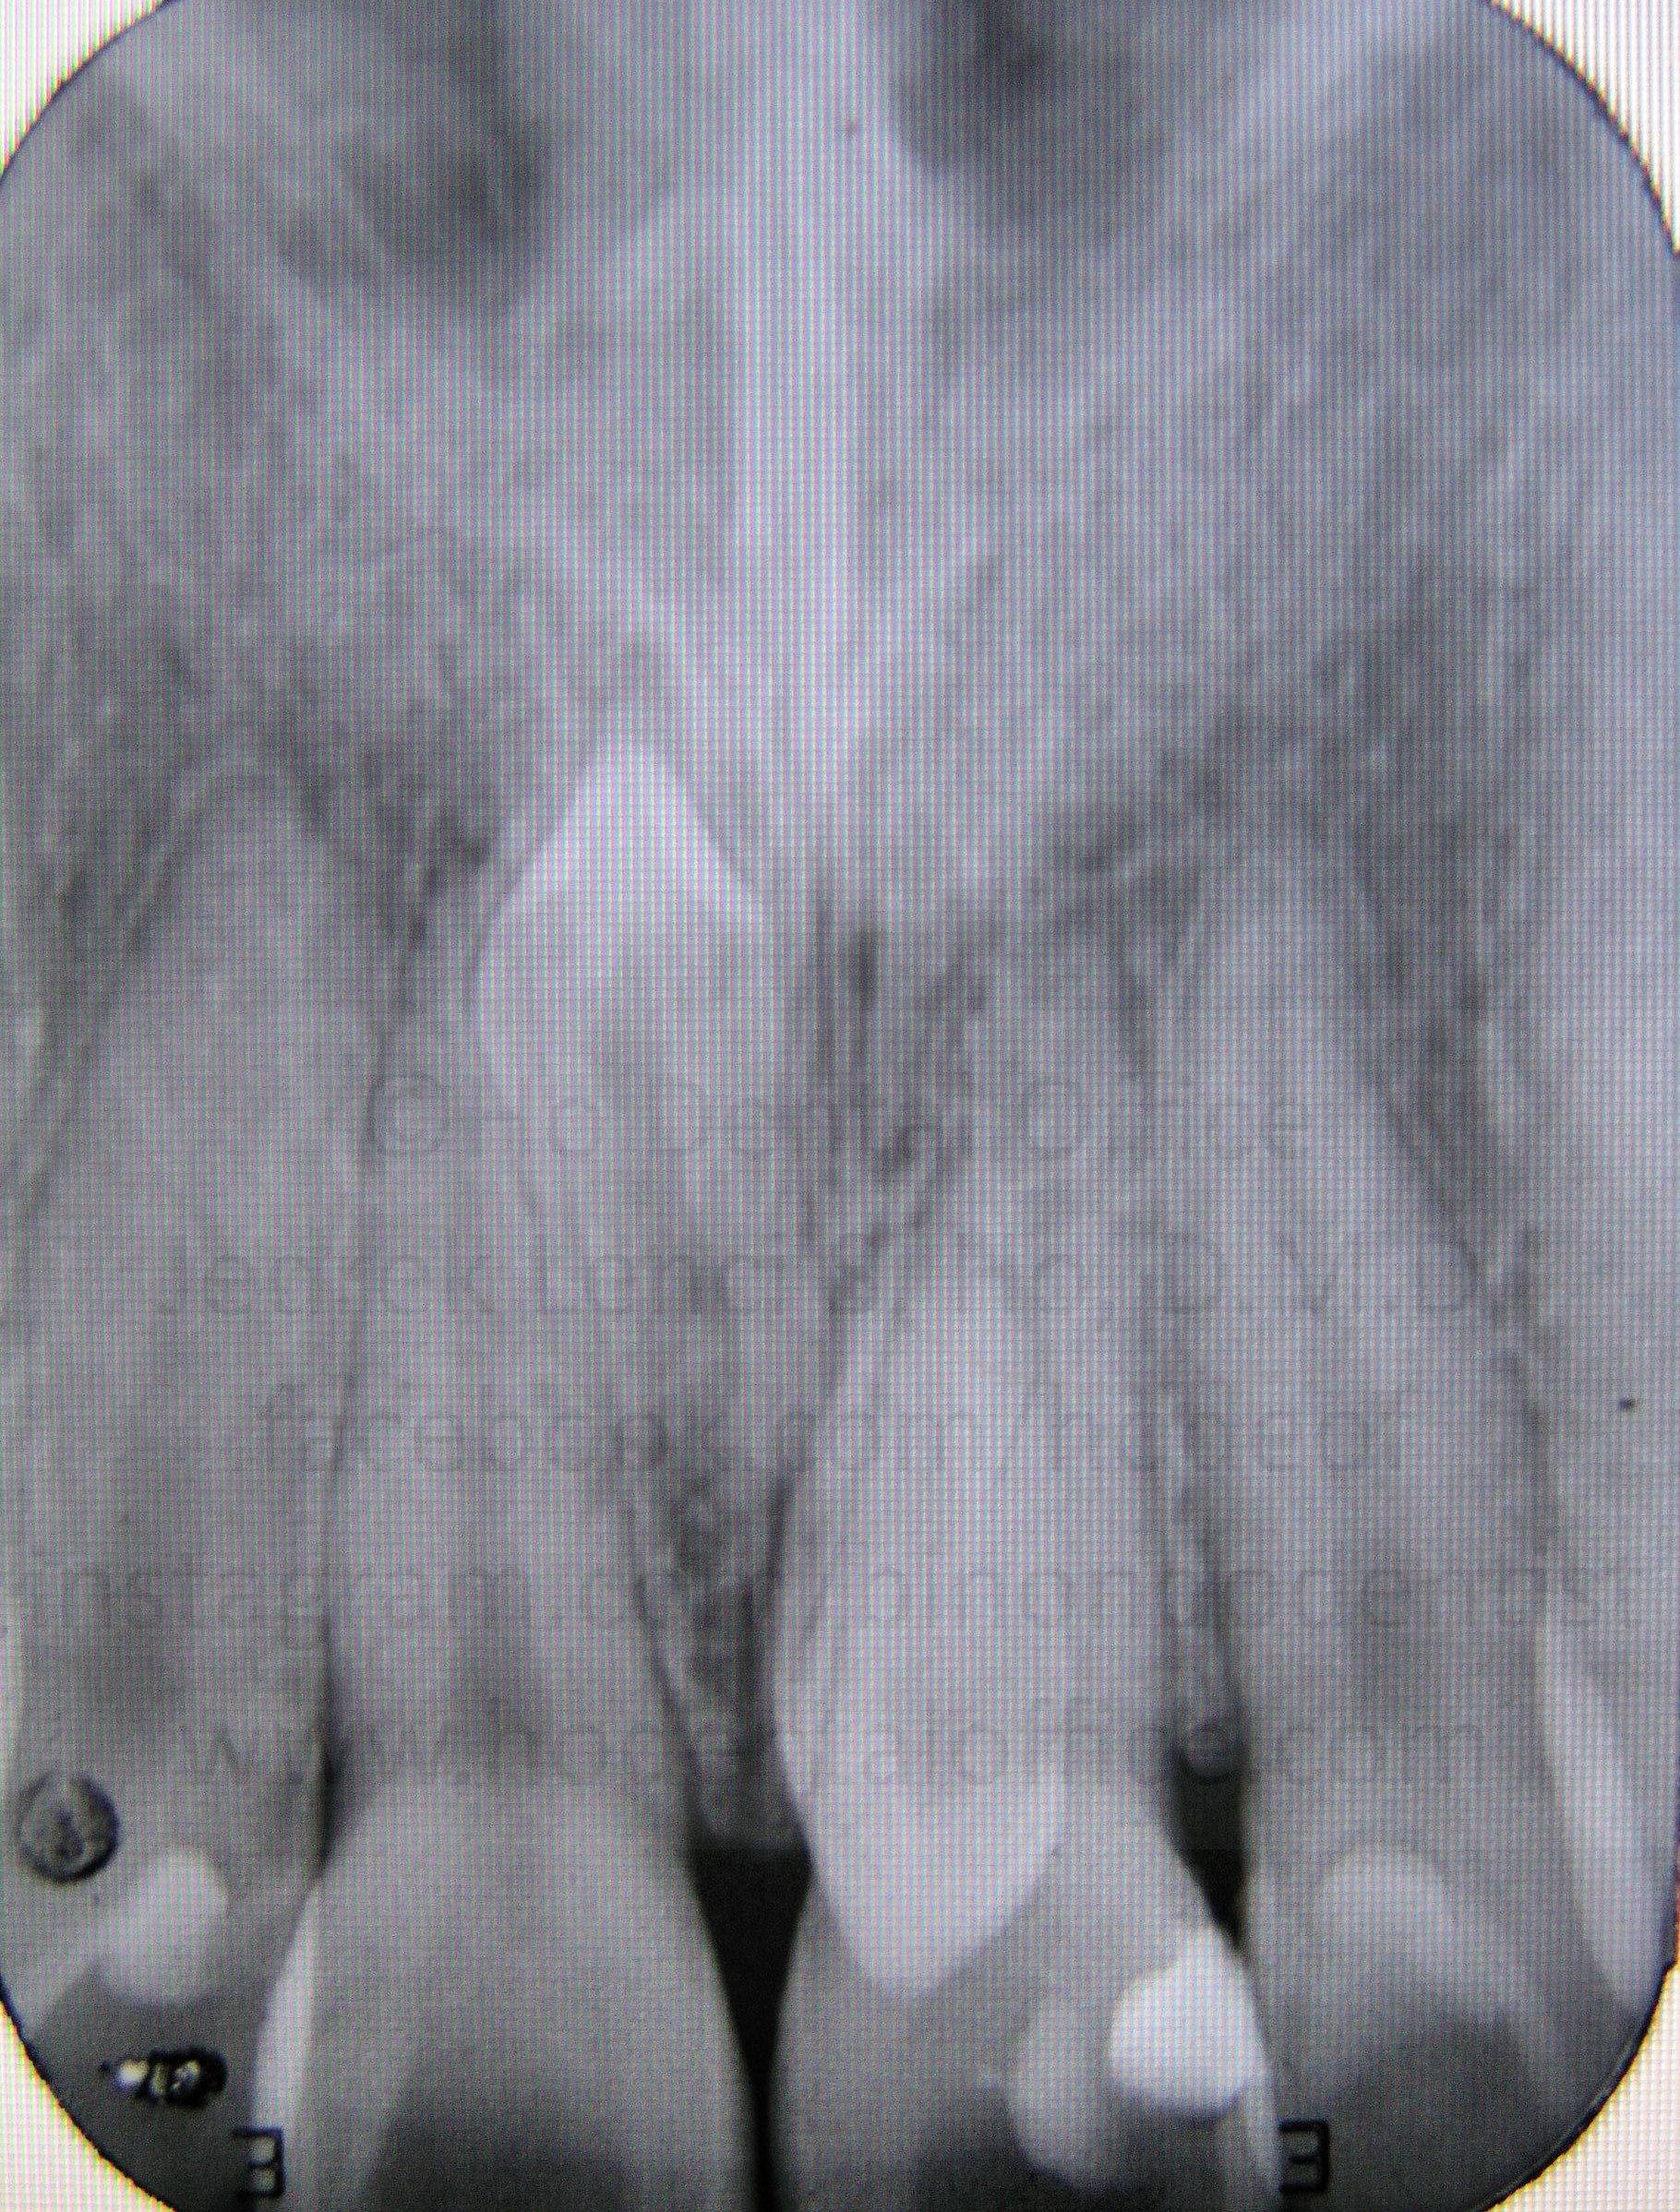

Upon observation, a very big frenum attachment is evident, with the "pull" of the muscle fibers (seen while stretching the lips) reaching all the way up to the incisive papilla on the back of the upper incisors. Patient was also checked with x-ray to ascertain presence of impacted teeth, if any.

X-ray results shows no signs of impacted teeth in between the two incisors. This area is common to having an impacted "mesiodens" - a supernumerary (extra) tooth - literally meaning a "tooth in the middle".

Since the cause of the diastema (big gap in the middle) was determined to be not caused by a hidden impacted tooth, it is highly likely that the strong frenum muscle attachment was the one causing it, as there have been documented cases similar to this that can be seen on dental textbooks and scientific papers.